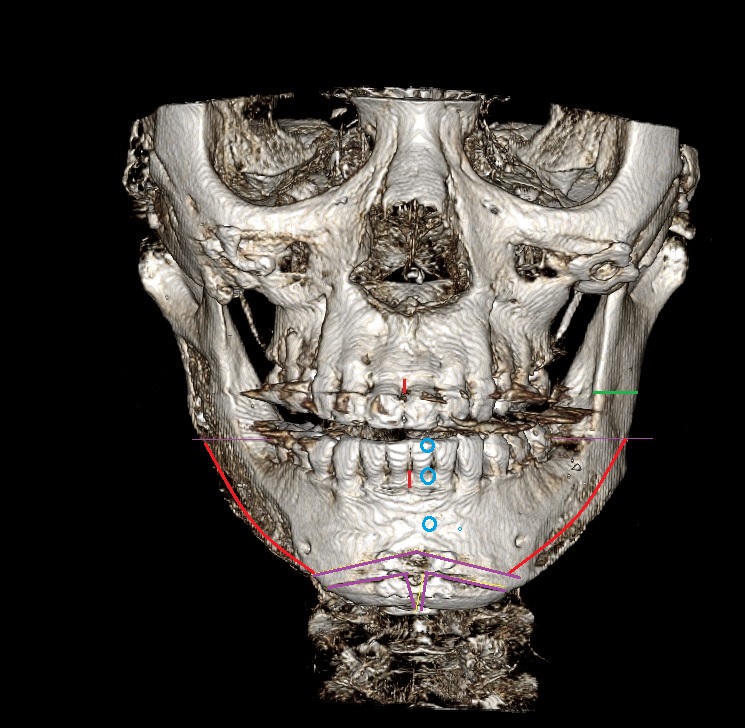

1. 현재 제가 수술 전후 ct를 올리겠습니다

2. 일차 양악 수술후 경미한 주걱턱 때문에 쉐이빙을 했는데 효과는 미미했습니다 진짜 쉐이빙은 효과가 미흡

3. 그 후 어드벤스를 3mm정도 했습니다

4. 현재 주걱턱 처럼 보여서 돌아버리겠습니다..

5. 음 어느 선생님 말을 빌리면 턱끝 절골라인이 너무 아래서 절골되어서 그런거다 신경선으로 부터 5~10mm정도 아래서 절골후 약간 사선으로 2mm 정도만 전진시키면 두꺼운 근육이 얇아지면서 좀 편해진다 이게 맞는말인가요???

6. 아니면 지금 상태에서 다시 절골한곳 다시 절골해서 뒤로 후퇴시켜야되나요?

7. 지금 현재 턱끝 포지션은 좋은가요?

8. 아래 제가 도완 한 대로 수술하면 어떨까요? 길이도 줄이면서 후퇴도 시키고